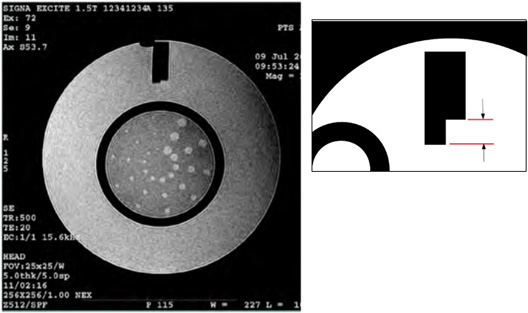

Slice Position Accuracy

The slice position accuracy test assesses the accuracy with which slices can be prescribed at specific locations utilizing the localizer image for positional reference.

Slices 1 and 11 were prescribed to be aligned with the vertices of the crossed 45 degree wedges at the inferior and superior ends of the phantom respectively. On the images of slices 1 and 11 the crossed wedges appear as a pair of adjacent, dark vertical bars at the top (anterior side) of the phantom. See illustration below. A perfectly positioned slice’s image shows a dark bar pair with left and right sides of equal vertical length. If the slice is displaced superiorly with respect to the vertex, the bar on the observer’s right (anatomical left) is longer. If the slice is displaced inferiorly with respect to the vertex, the bar on the left (anatomical right) will be longer.

Referring to Figure 18, use the on-screen length measurement tool to measure the difference in vertical lengths between the left & right bars of the cross wedge in mm.

Record the difference (as a negative value if the left bar is longer) as ACR T1 Slice 1 Bar Length Difference (mm). Use the ACR Accreditation Scan Measurements form to record the values.